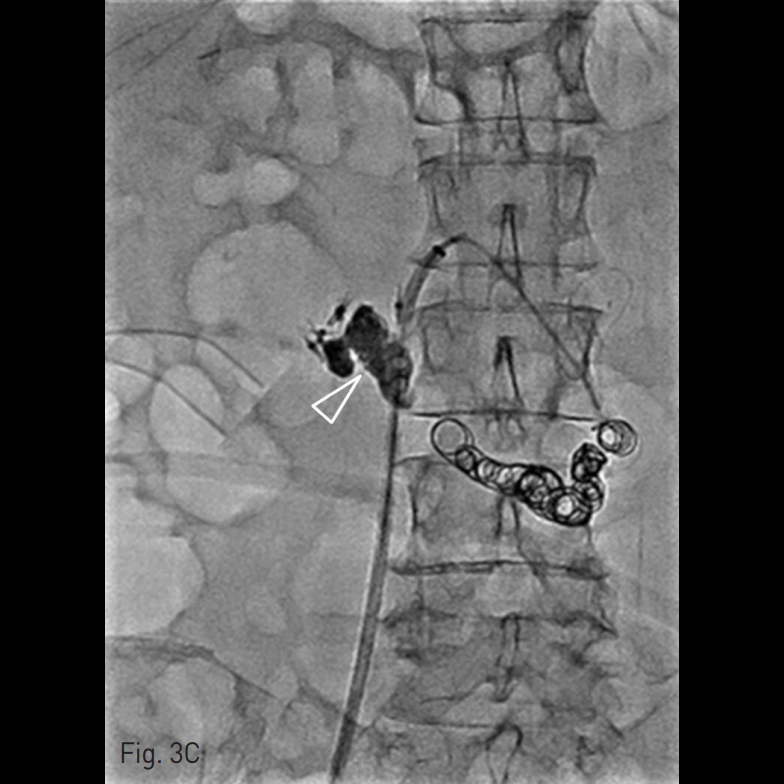

간암과 간경화로 간이식술을 받음. 수술 16일째에 대량의 흑색변이 발견되고 혈액검사에서 혈색소 감소(hemoglobin 11.3g/dL → 9.1g/dL) 가 확인되어 소화관 내시경 검사를 받았음. 내시경 검사상 십이지장 상부하행각 (superior descending angle)에서 출혈을 동반한 궤양이 발견되어 발견 당일과 4일 후 두 차례에 걸쳐 hemoclip을 이용한 내시경적 결찰술 및 경화요법으로 치료했으나(Fig. 1) 혹색변과 혈색소 감소는 교정되지 않아 지속적인 수혈요법을 받고 있었음.

Fig. 1

Duodenal ulcer-like lesion with current bleeding is seen at superior descending angle of duodenum. Endoscopic hemostasis with hemoclip was attempted for the lesion.